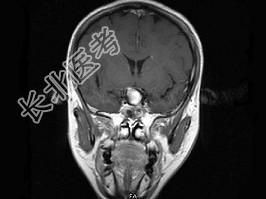

- 单项选择题女,43岁, 反复头痛10个月,CT检查如图, 最可能的诊断是 ( )